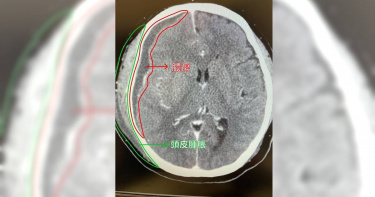

一名49歲設備工程師,過去有大腸癌病史,牙齦疼痛兩天,頸部及眼部腫脹,陸續出現脖子和眼睛腫脹,發燒,呼吸困難,意識模糊等症狀,到中國醫藥大學新竹附設醫院急診,經抽血及頭頸部電腦斷層檢查,神經外科巫智穎醫師診斷為深頸感染併發牙齦及眼眶感染。由於病患病程進展快速,引發敗血性休克,顱內膿瘍,呼吸衰竭,於加護病房治療期間,施予經鼻氣管內管置入,後線抗生素及升壓劑治療,神經外科巫智穎醫師以開顱併內膿瘍清除手術。經兩個月治療之後,患者不僅脫離呼吸器沒有插管,意識也恢復清醒,手腳活動無礙,眼睛及頸部腫脹消失,唯膿瘍跑到眼睛造成視力模糊的後遺症。巫智穎醫師表示,深頸感染發生在比較深層的感染,比較不好醫治,死亡率高達五成以上。一開始通常發生在口頸,例如蛀牙、牙齦感染、拔牙感染,中耳炎、鼻塞、上呼吸道感染等,如果服藥5-7天症狀都沒有改善,反而越來越痛,甚至合併高燒不退,呼吸窘迫等症狀,代表感染侵犯到深層的頸部肌肉層,造成細菌大量滋長,往上會延伸到眼睛甚至顱內,往下延伸至靠近心肺的縱膈腔。感染過程中,如果以為只是小病不去治療,會造成呼吸道壓迫、敗血性休克,甚至會有馬上致命的危險。 巫智穎醫師強調,深頸感染好發在免疫力低下的族群,特別是老人、幼童、癌症、糖尿病、腎衰竭的患者,因為本身防護力不夠,往往認為的小病都可能蔓延成致命性的疾病。治療方面以抗生素治療為主,如果感染控制不良或者侵犯腦部造成腫塊效應,就要加以手術清創治療,不可不慎。